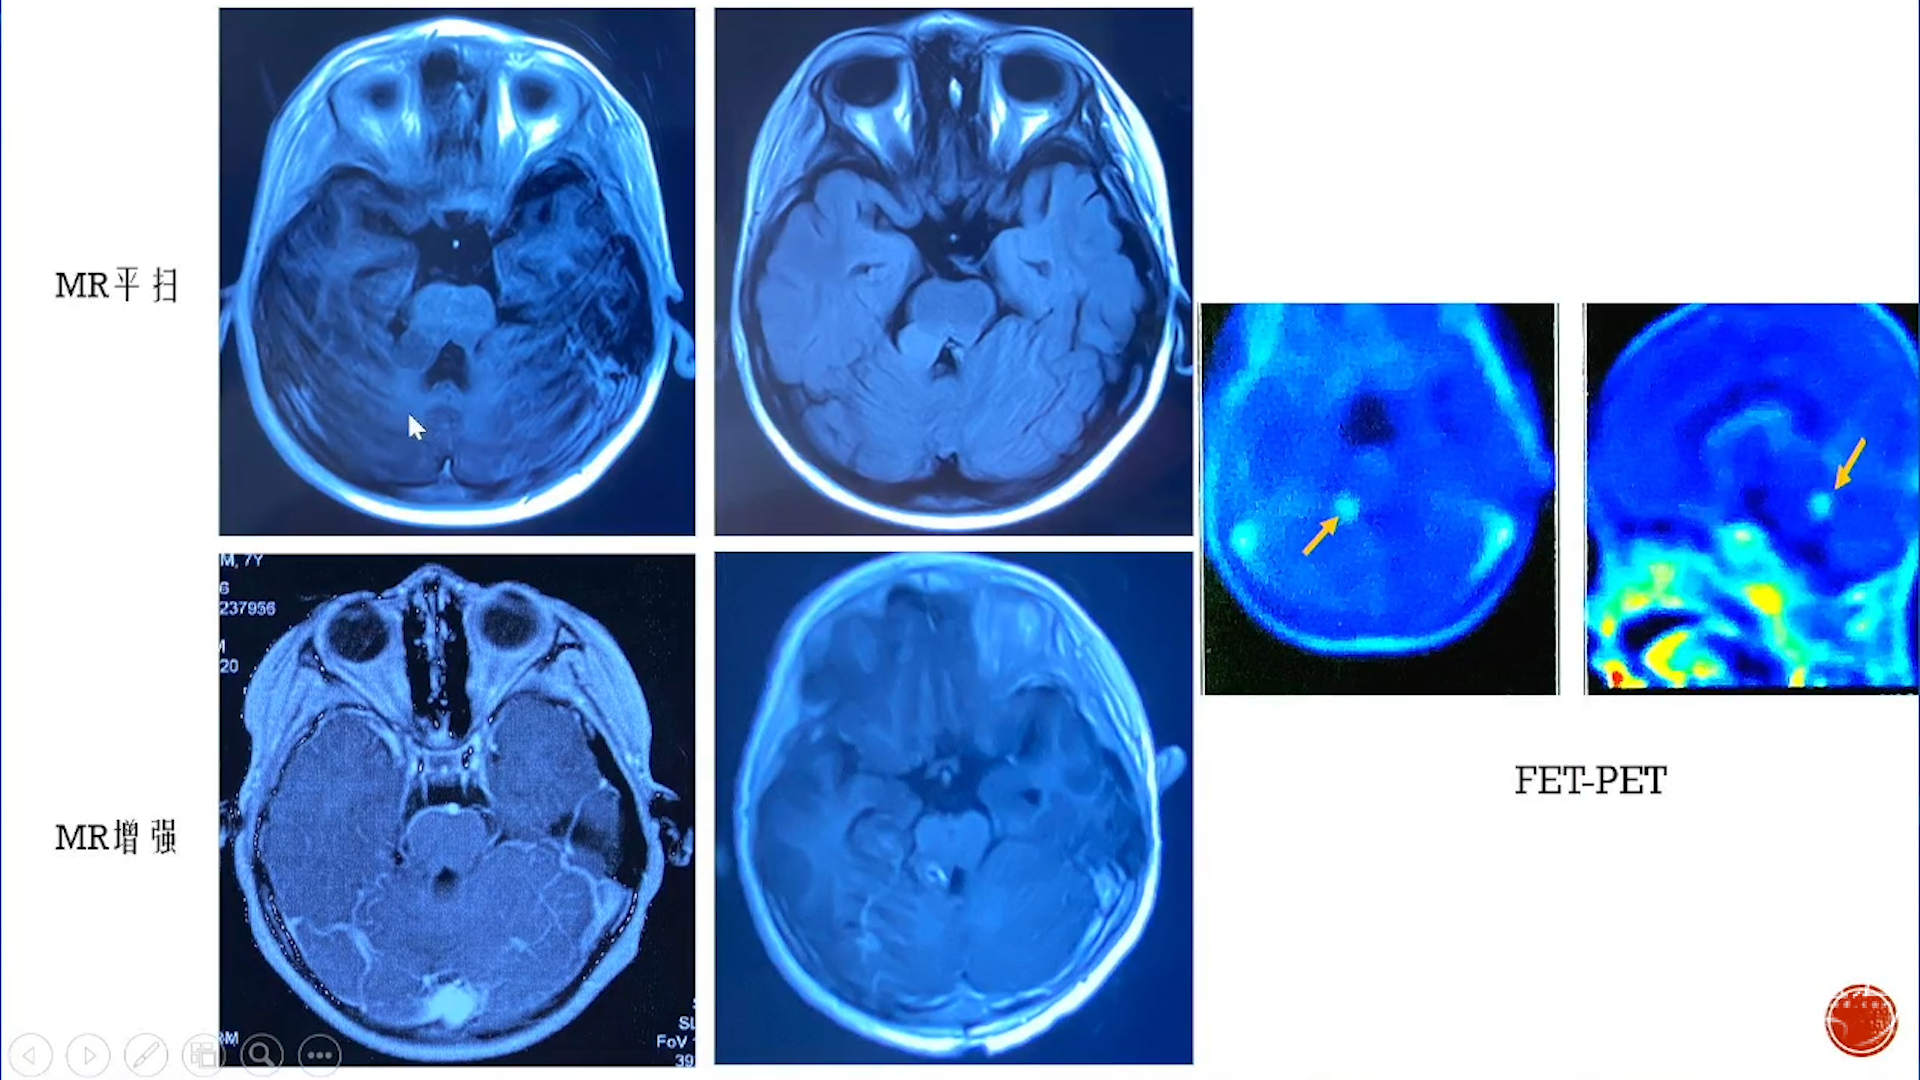

小脑星形细胞肿瘤

大脑半球儿童低级别胶质瘤

·致痫性肿瘤局限性肿瘤:节细胞胶质瘤、胚胎发育不良性神经上皮肿瘤(DNT)等

·弥漫性肿瘤